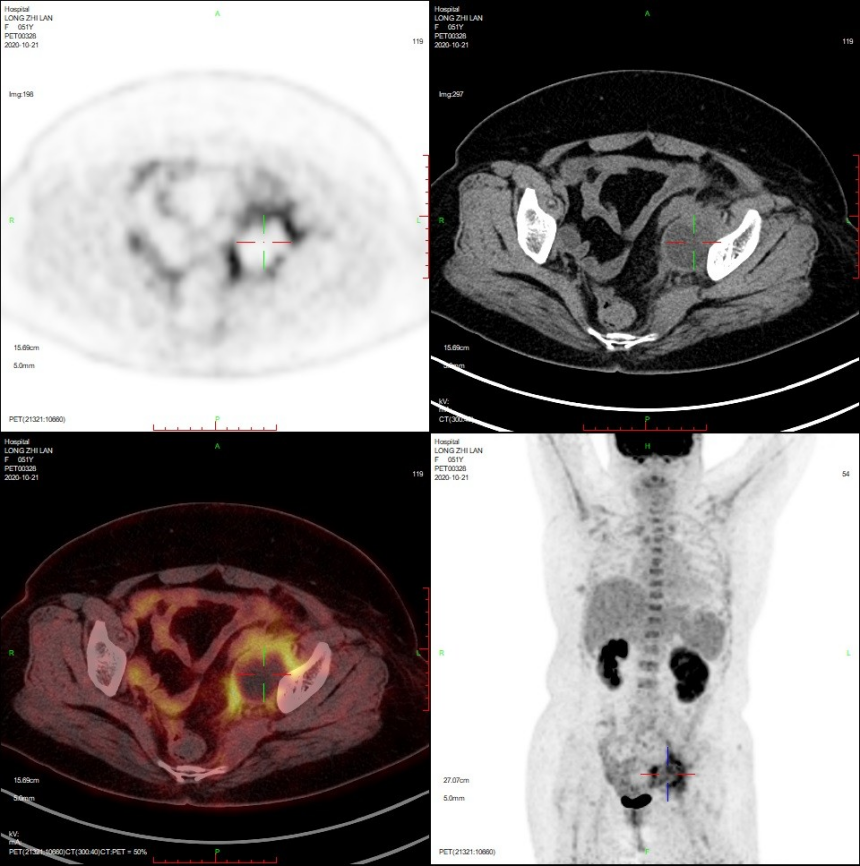

✦主诉:子宫内膜癌(2期)术后4月,放化疗后腹部伴下肢疼痛一个月。